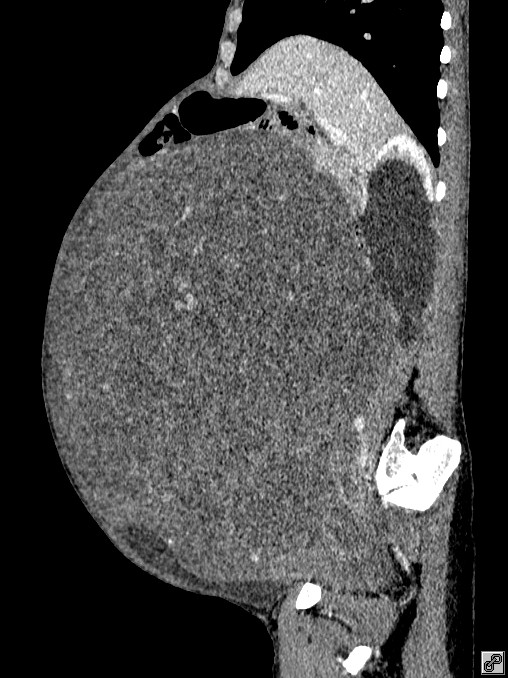

手术前患者的CT影像图。

意识到有问题,家人赶紧带着王阿姨来到广医三院看病。随后,检查结果震惊了家人——王阿姨的子宫长了一个巨大的肿物,占满了整个盆腹腔!医生初步判断可能是子宫肌瘤。

近日,广州55岁王阿姨因肚子异常隆起,被家人带来广州医科大学附属第三医院就诊。医生一检查竟发现,王阿姨肚子里长了一个巨大的子宫肌瘤,直径足有40cm,比西瓜还大,占满了整个盆腹腔。

幸运的是,凭借充分的术前准备和多学科专家的密切配合,终于完整切除了肿物。医护人员对切下来的肿物进行测量发现,这个巨型的肌瘤,最长处直径超过40cm,竟然重达16.5kg(33斤左右),相当于5个足月胎儿重量的总和!这么一个巨型“*弹炸**”,幸亏顺利取出了。